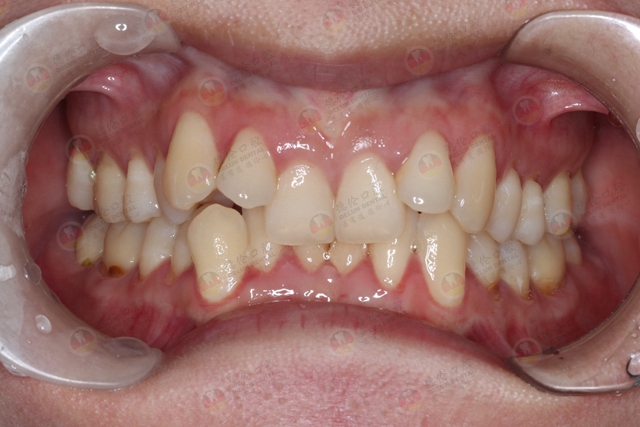

1、拥挤牙齿

当牙齿数量多于口腔空间时,牙齿就会变得拥挤。这种情况下,牙齿可能会相互重叠或扭曲,导致不整齐的外观和咬合问题。

2、错位牙齿

当牙齿在牙槽骨中生长时,可能会出现位置偏差。这种情况下,牙齿可能会错位或旋转,导致不整齐的外观和咬合问题。